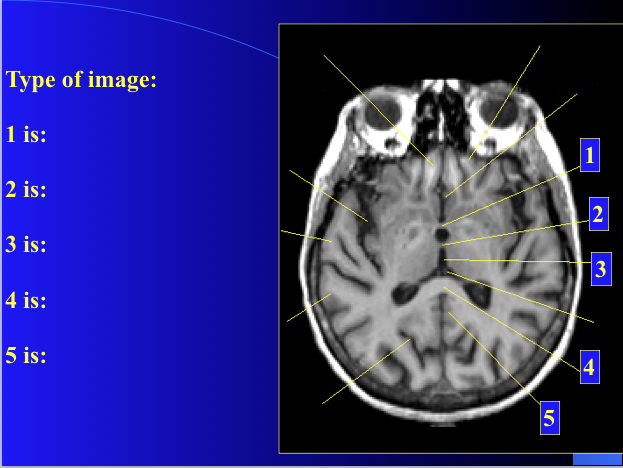

Is this T1 or T2?

T-1

1) anterior commissure

2) interthalamic adhesion

3) third ventricle

4) spleneium

5) cingulate gyrus